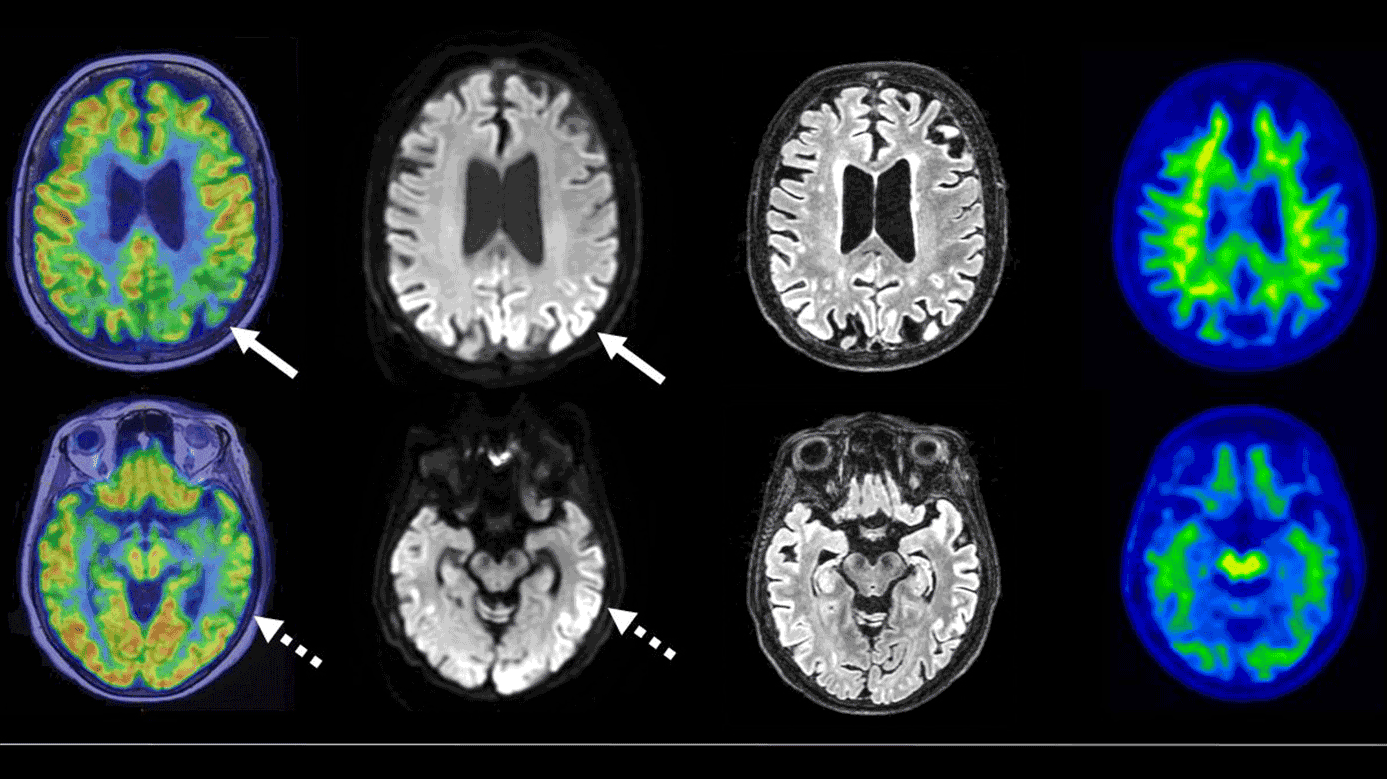

På klinisk mistanke om en blanding af Alzheimers sygdom (AD) og vaskulær demens blev patienten henvist til en kombineret 18F-fluordeoxyglukose (FDG)-PET/MR-skanning. I samme periode blev hun indlagt på psykiatrisk afdeling og udskrevet igen efter behandling af svær depression. 18F-FDG-PET viste nedsat FDG-optagelse parietotemporalt, primært venstresidigt, hvilket umiddelbart kunne ligne et AD-mønster. MR-skanning påviste dog karakteristiske kortikale hyperintensiteter på diffusion-weighted imaging (DWI)/fluid-attenuation inversion recovery (FLAIR)-sekvenser i samme områder, hvilket kan ses ved Creutzfeldt-Jakobs sygdom (CJD). Normale AD-biomarkører i spinalvæsken og negativ 11C-Pittsburgh compound B (PiB)-PET udelukkede betaamyloid patologi. CJD-diagnosen blev endeligt bekræftet ved en positiv real-time quaking-induced conversion (RT-QuIC)-test.

Ved CJD kan prionproteininduceret celledød forårsage både nedsat neuronal aktivitet (18F-FDG-PET) og diffusionsrestriktion (DWI) i samme områder. Kombineret PET/MR-skanning kan bidrage til tidligere og mere præcis diagnostik af kognitive forstyrrelser [1]. Behandlingen af CJD er udelukkende symptomlindrende og støttende.